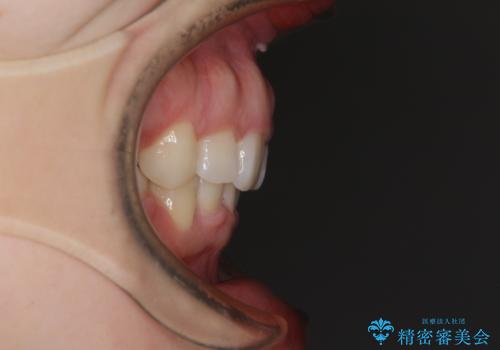

目立たない裏側矯正 抜歯矯正で口元を改善

- 前歯のデコボコと上顎の前突感による口の閉じにくさを気にして来院された患者様です。

目立たない装置を希望されたので、上顎が裏側装置のハーフリンガルを選択し、上下左右の小臼歯(計4歯)を抜歯して矯正治療を行うこととしました。

治療期間の目安は2年半~3年間でしたが、咬み合わせにより上顎装置が頻繁に脱落してしまい、治療期間が長期化してしまいました。

期間はかかったものの、口元の張り出し感や歯のデコボコが解消され、患者様には大変満足していただけました。